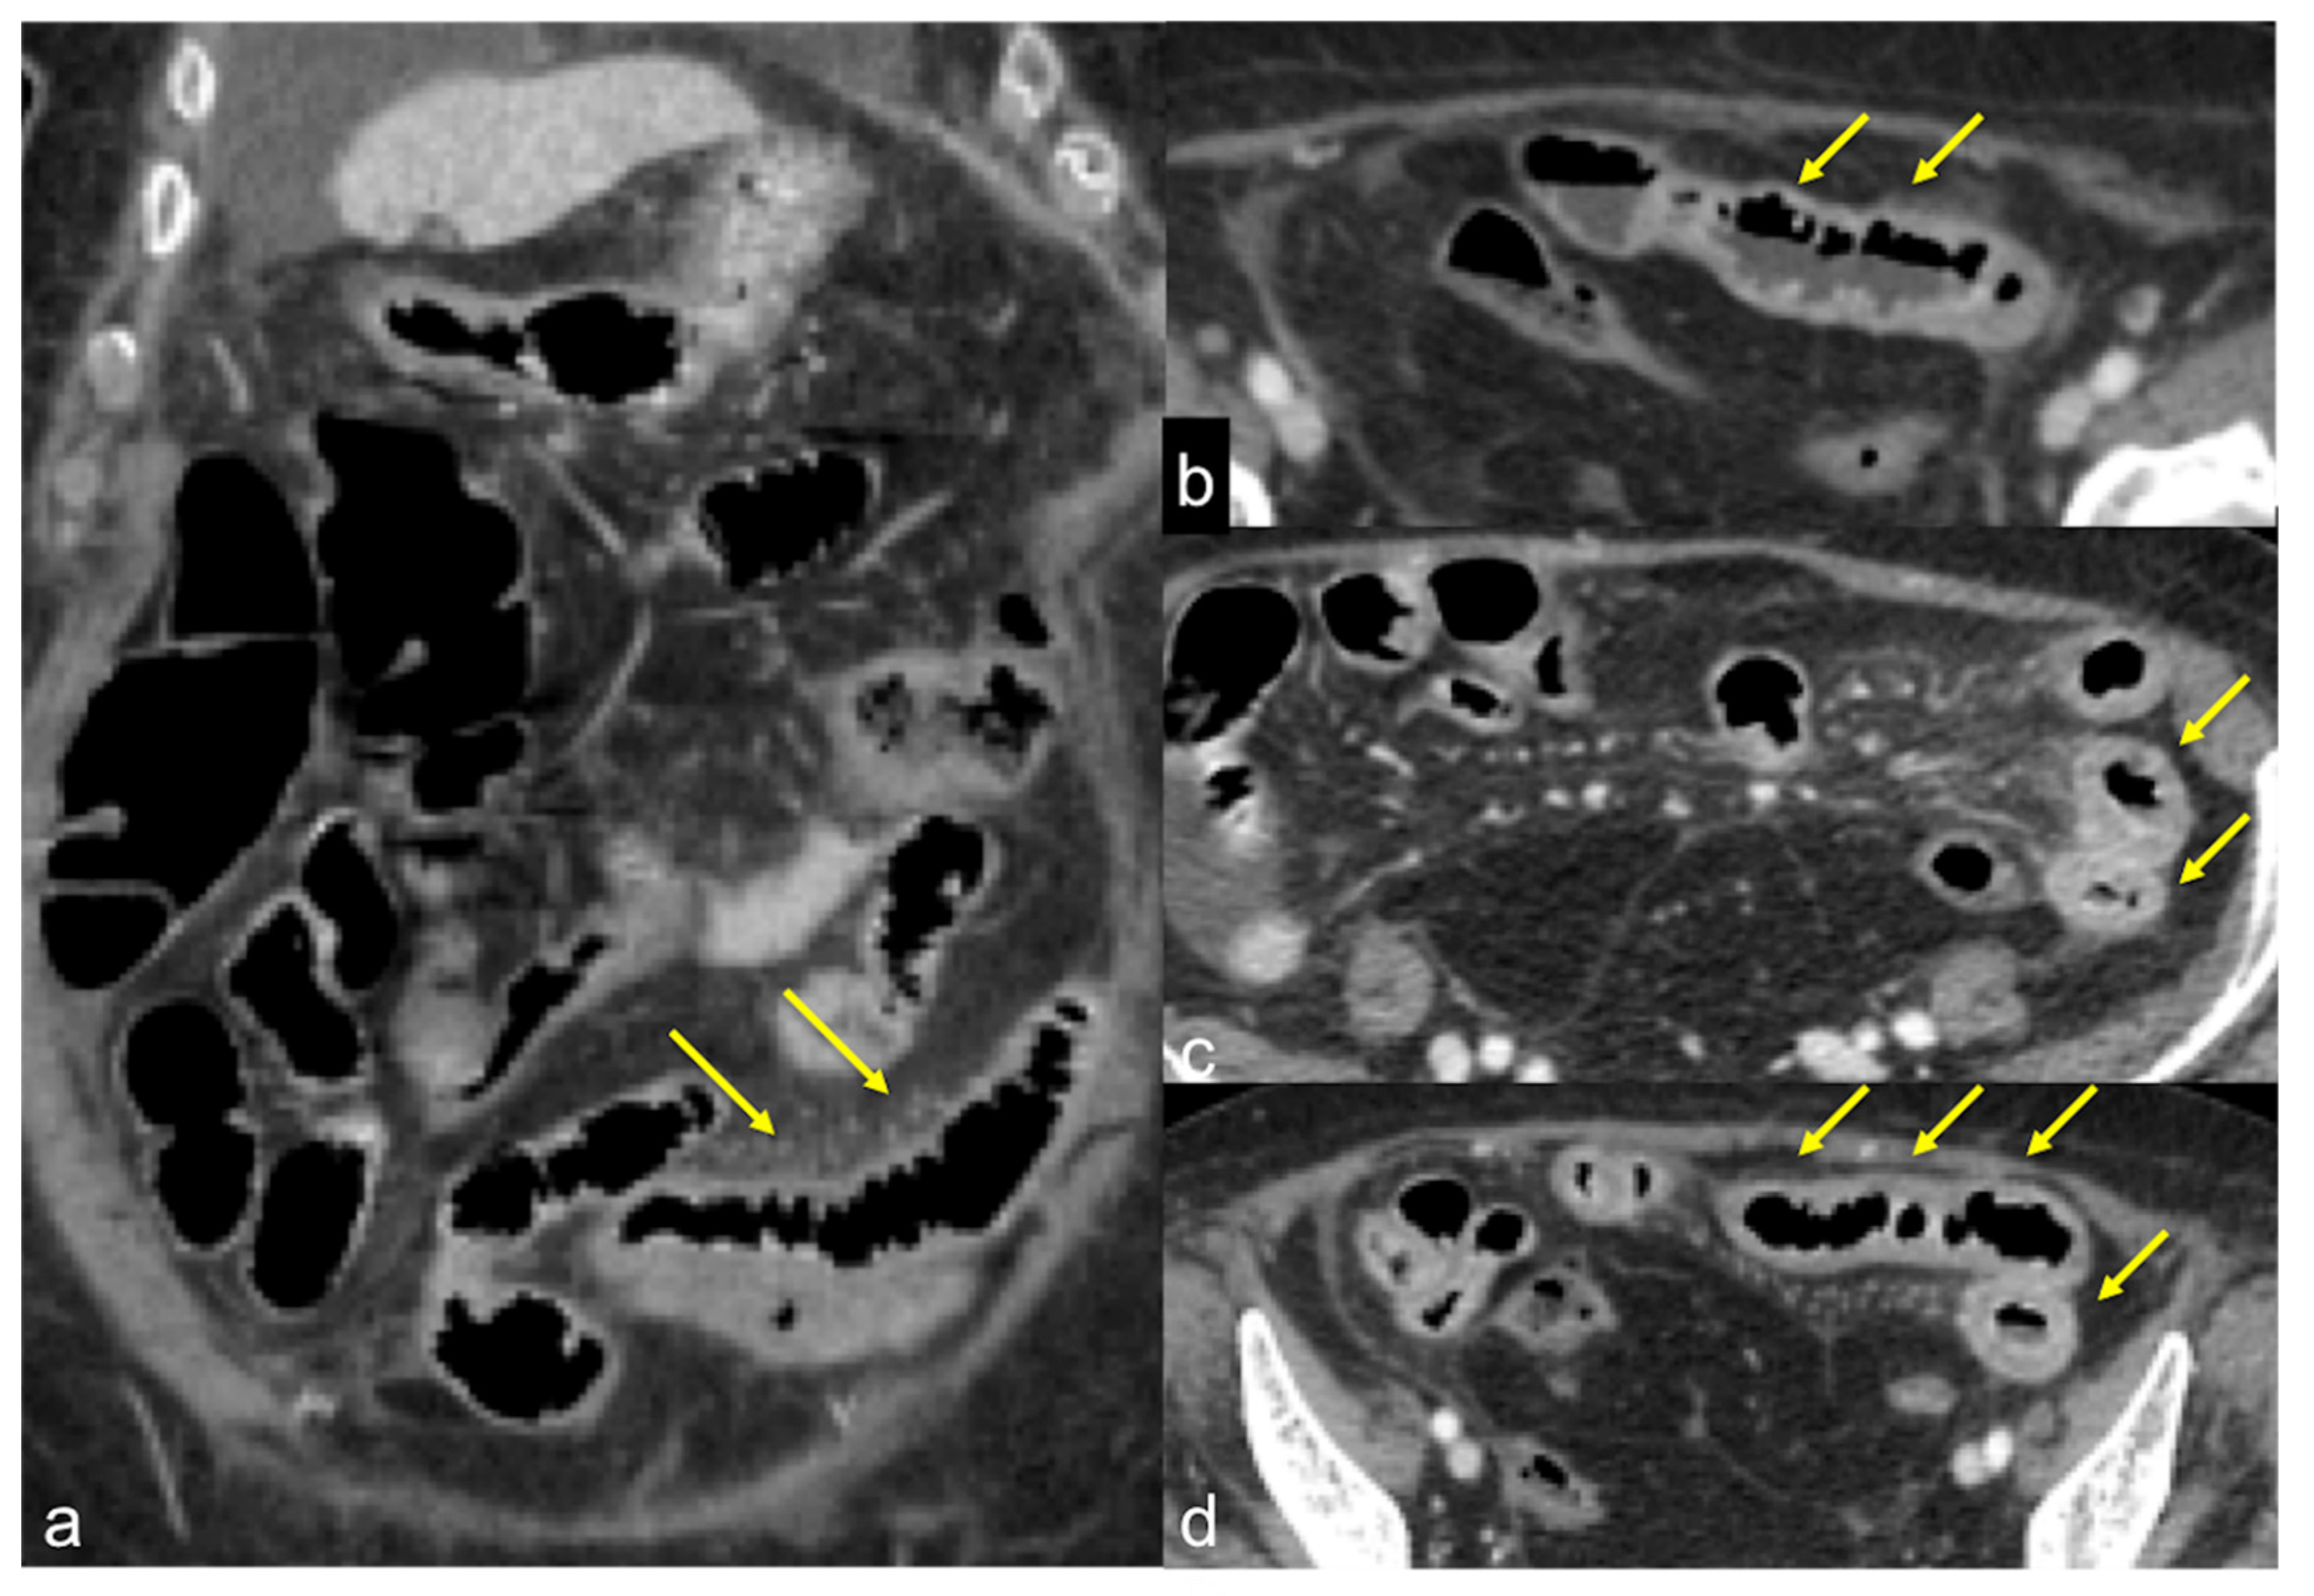

| Inflammatory Bowel Disease (Figure 39 and Figure 40) | Haematochezia-rectorrhagia. | Acute: thickening of the walls, engorgement of the adjacent vasa recta, hyperaemia of the mucosa and infiltration of perirectal fat. Chronic: the colon and rectum are narrowed and shortened, without haustra, and with proliferation of the perirectal fat. |